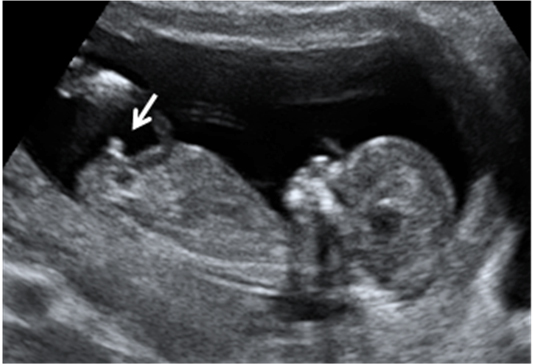

Ecografía 4D semana 12: Bebé con cordón umbilical al cuello

El cordón "sube" por el tórax del bebé

La ecografía en tres dimensiones muestra un feto de 13 semanas de gestación con el cordón umbilical alrededor del cuello. En la imagen rotatoria se puede observar la situación del cordón, que sube por el tórax y que seguramente puede causar complicaciones en el embarazo.